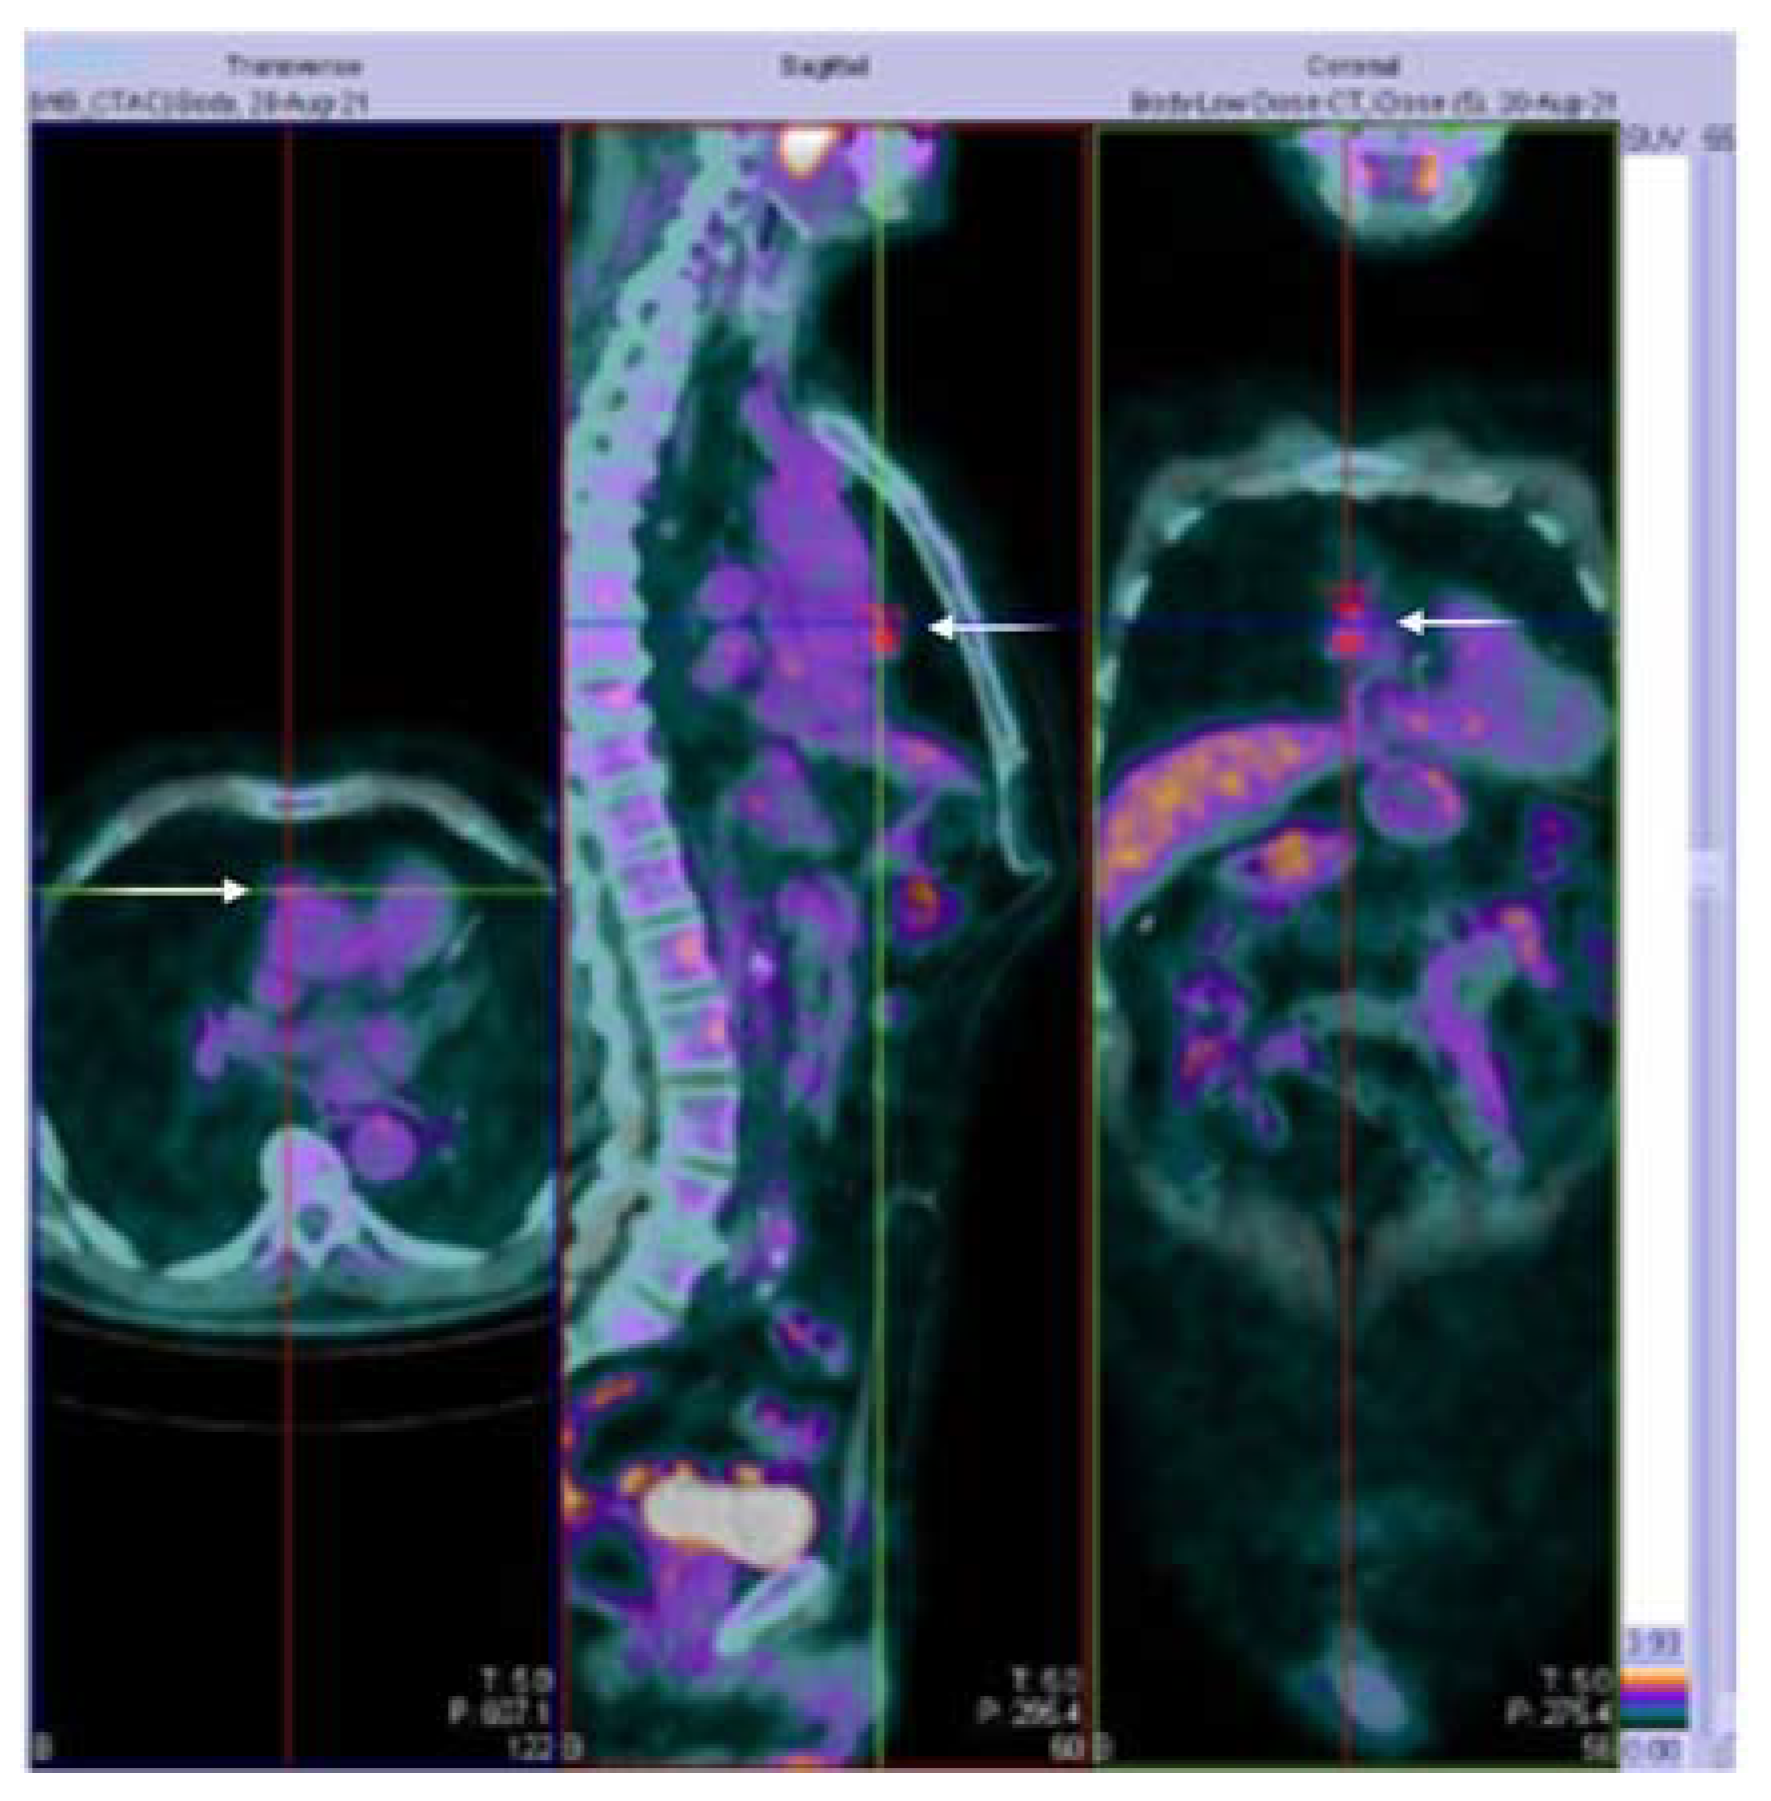

| 26 * | 73/M | O.A ChAdOx1/1° | 28 | AchR+ | Diplopia | Generalized | P360 mg/S12.5 mg/AZA | Improvement | T |